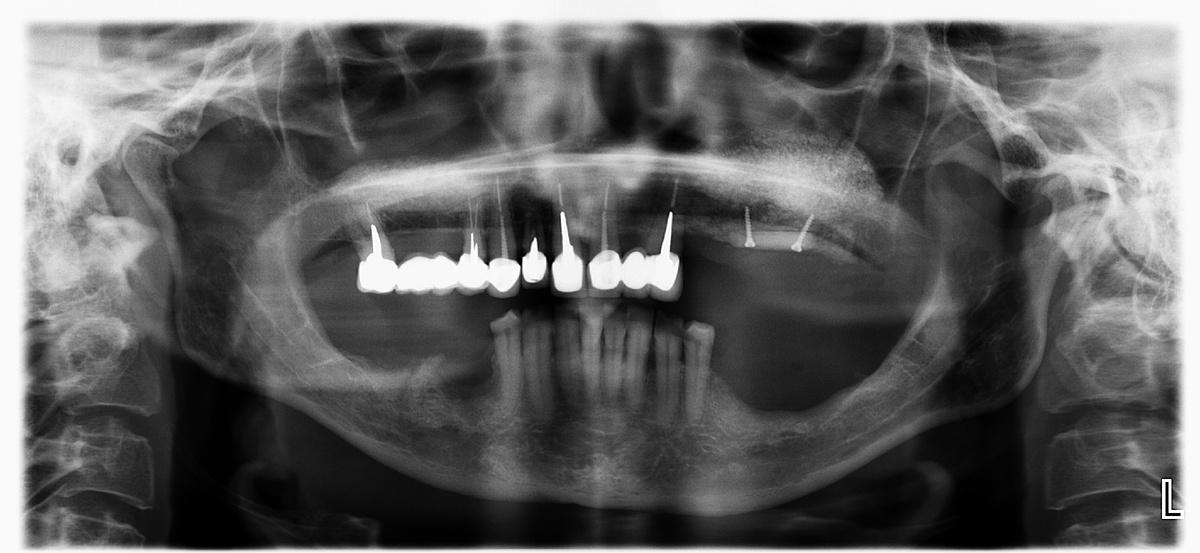

Следующий шаг — реконструкция костной ткани верхней и нижней челюсти. На снимке ОПТГ обозначены области проведенной остеопластики

Верхняя челюсть

Классический «открытый» синус-лифтинг в области 5 и 6 зубов справа (№1 на снимке ОПТГ). Подготовка для будущей имплантации в этом сегменте.

Слева — комбинированный протокол— «открытый» синус-лифтинг и каркасная пластика титановой сеткой (№2 на снимке ОПТГ) для восстановления альвеолярного гребня по высоте.

Синус-лифтинг слева и справа провели за 1 визит

Операция длилась 4 часа, проводилась в седации

Синус-лифтинг выполнен с применением пьезохирургического аппарата

Костный материал — собственная аутокость в сочетании с натуральным костнозамещающим материалом «Bio-Oss»

Результат на снимке ОПТГ:

Нижняя челюсть

Справа проводим пластику кости по высоте и ширине специальной «каркасной» техникой остеопластики титановой сеткой (№3 на снимке ОПТГ), которую применяем при экстремальной атрофии костной ткани челюсти

Слева на нижней челюсти наращиваем костный объем с помощью костных блоков (№4 на снимке ОПТГ)

Остеопластика слева и справа была проведена за 1 визит

Операция длилась 6 часов, проводилась в седации

Костный материал — костные блоки, аутогенная костная стружка в сочетании с натуральным костнозамещающим материалом Bio-Oss

Остеопластика на нижней челюсти на снимке ОПТГ